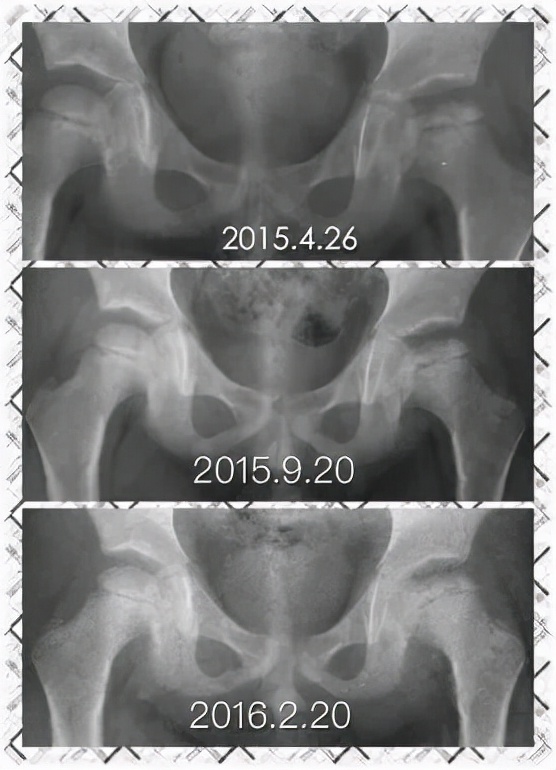

Perthes病即 儿童股骨头特发性缺血性骨软骨病,于1910年被Legg、Calve、和Perthes三位学者总结报道,因此也称为Legg-Calve-Perthes病,简称LCPD。发病早期,患儿往往出现跛行和患侧大腿中下段的疼痛不适、有时甚至是健侧膝盖周围疼痛,休息几天就可以缓解。但由于儿童天性活泼好动,上述症状常常容易复发。因此好多孩子常常被家长乃至初诊医生忽视、只是简单认为是“滑膜炎”、“缺钙”或者所谓“生长痛”,没有早期发现并且及时确诊、科学施治,而遗留了头臼曲率适应不佳、髋臼覆盖不良、股骨近端形态异常等等生长发育畸形(图1),导致髋关节出现软骨磨损继而早发骨性关节炎,从而严重影响日常生活和工作。而如果能够早发现早治疗,LCPD完全可以获得优良结果乃至正常髋关节状态(图2)!

图2 LCPD患者影像学变化